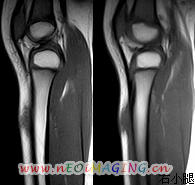

标题: PED0931:男,5岁,发现双小腿软组织肿块1年,质地中等,无 [打印本页]

标题: PED0931:男,5岁,发现双小腿软组织肿块1年,质地中等,无

多发性神经纤维瘤?

考虑多发性神经纤维瘤.